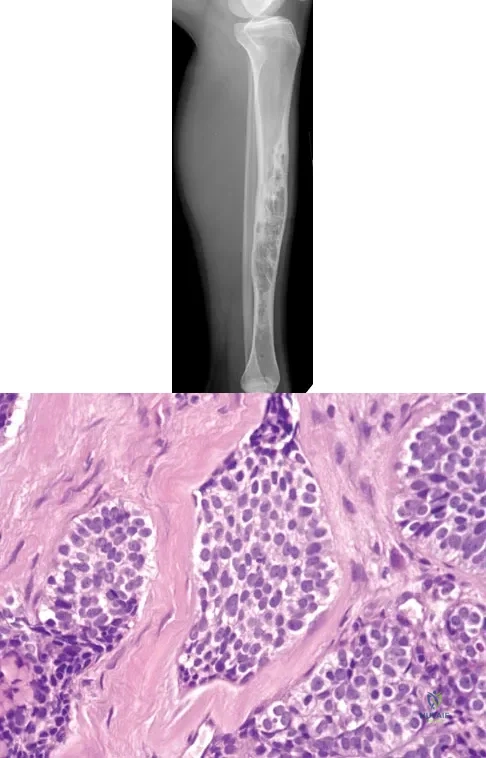

Question 18

A 30-year-old woman has had pain in her right leg for the past 6 months. A lytic lesion is noted in the anterior cortex of the midtibia, extending 5 cm in length without a soft-tissue mass. A radiograph and a biopsy specimen are shown in Figures 35a and 35b. What is the preferred treatment?